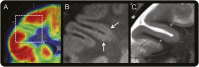

Methods: Retrospective review of clinical records, EEG, MRI, and histopathology in 32 patients with drug-resistant epilepsy and MRI-positive (72% 3.0 tesla), pathologically proven (type 2B cortical dysplasia) BOSDs operated at our centers during 2005-2013.

Results: Localization of BOSDs was frontal in 19, insula in 5, parietal in 5, and temporal in 3, on the convexity or interhemispheric surfaces. BOSDs were missed on initial MRI at our centers in 22% of patients. Patients presented with focal seizures during infancy in 9, preschool years in 15, and school years in 8 (median age 5 years). Seizures were stereotyped, predominantly nocturnal, and typically nonconvulsive, with semiology referable to the fronto-central or perisylvian regions. Seizures occurred at high frequency during active periods, but often went into prolonged remission with carbamazepine or phenytoin. Intellect was normal or borderline, except in patients with seizure onset during infancy. Scalp EEG frequently revealed localized interictal epileptiform discharges and ictal rhythms. Patients underwent lesionectomy (median age 14 years) guided by electrocorticography and MRI, with prior intracranial EEG monitoring in only one patient. Twenty-eight patients (88%) became seizure-free, and 20 discontinued antiepileptic medication (median follow-up 4.1 years).

Conclusions: In patients with cryptogenic focal epilepsy, this clinical presentation and course should prompt review of or repeat MRI, looking for a BOSD in the frontal, parietal, or insula cortex. If a BOSD is identified, the patient might be considered for single-stage lesionectomy.